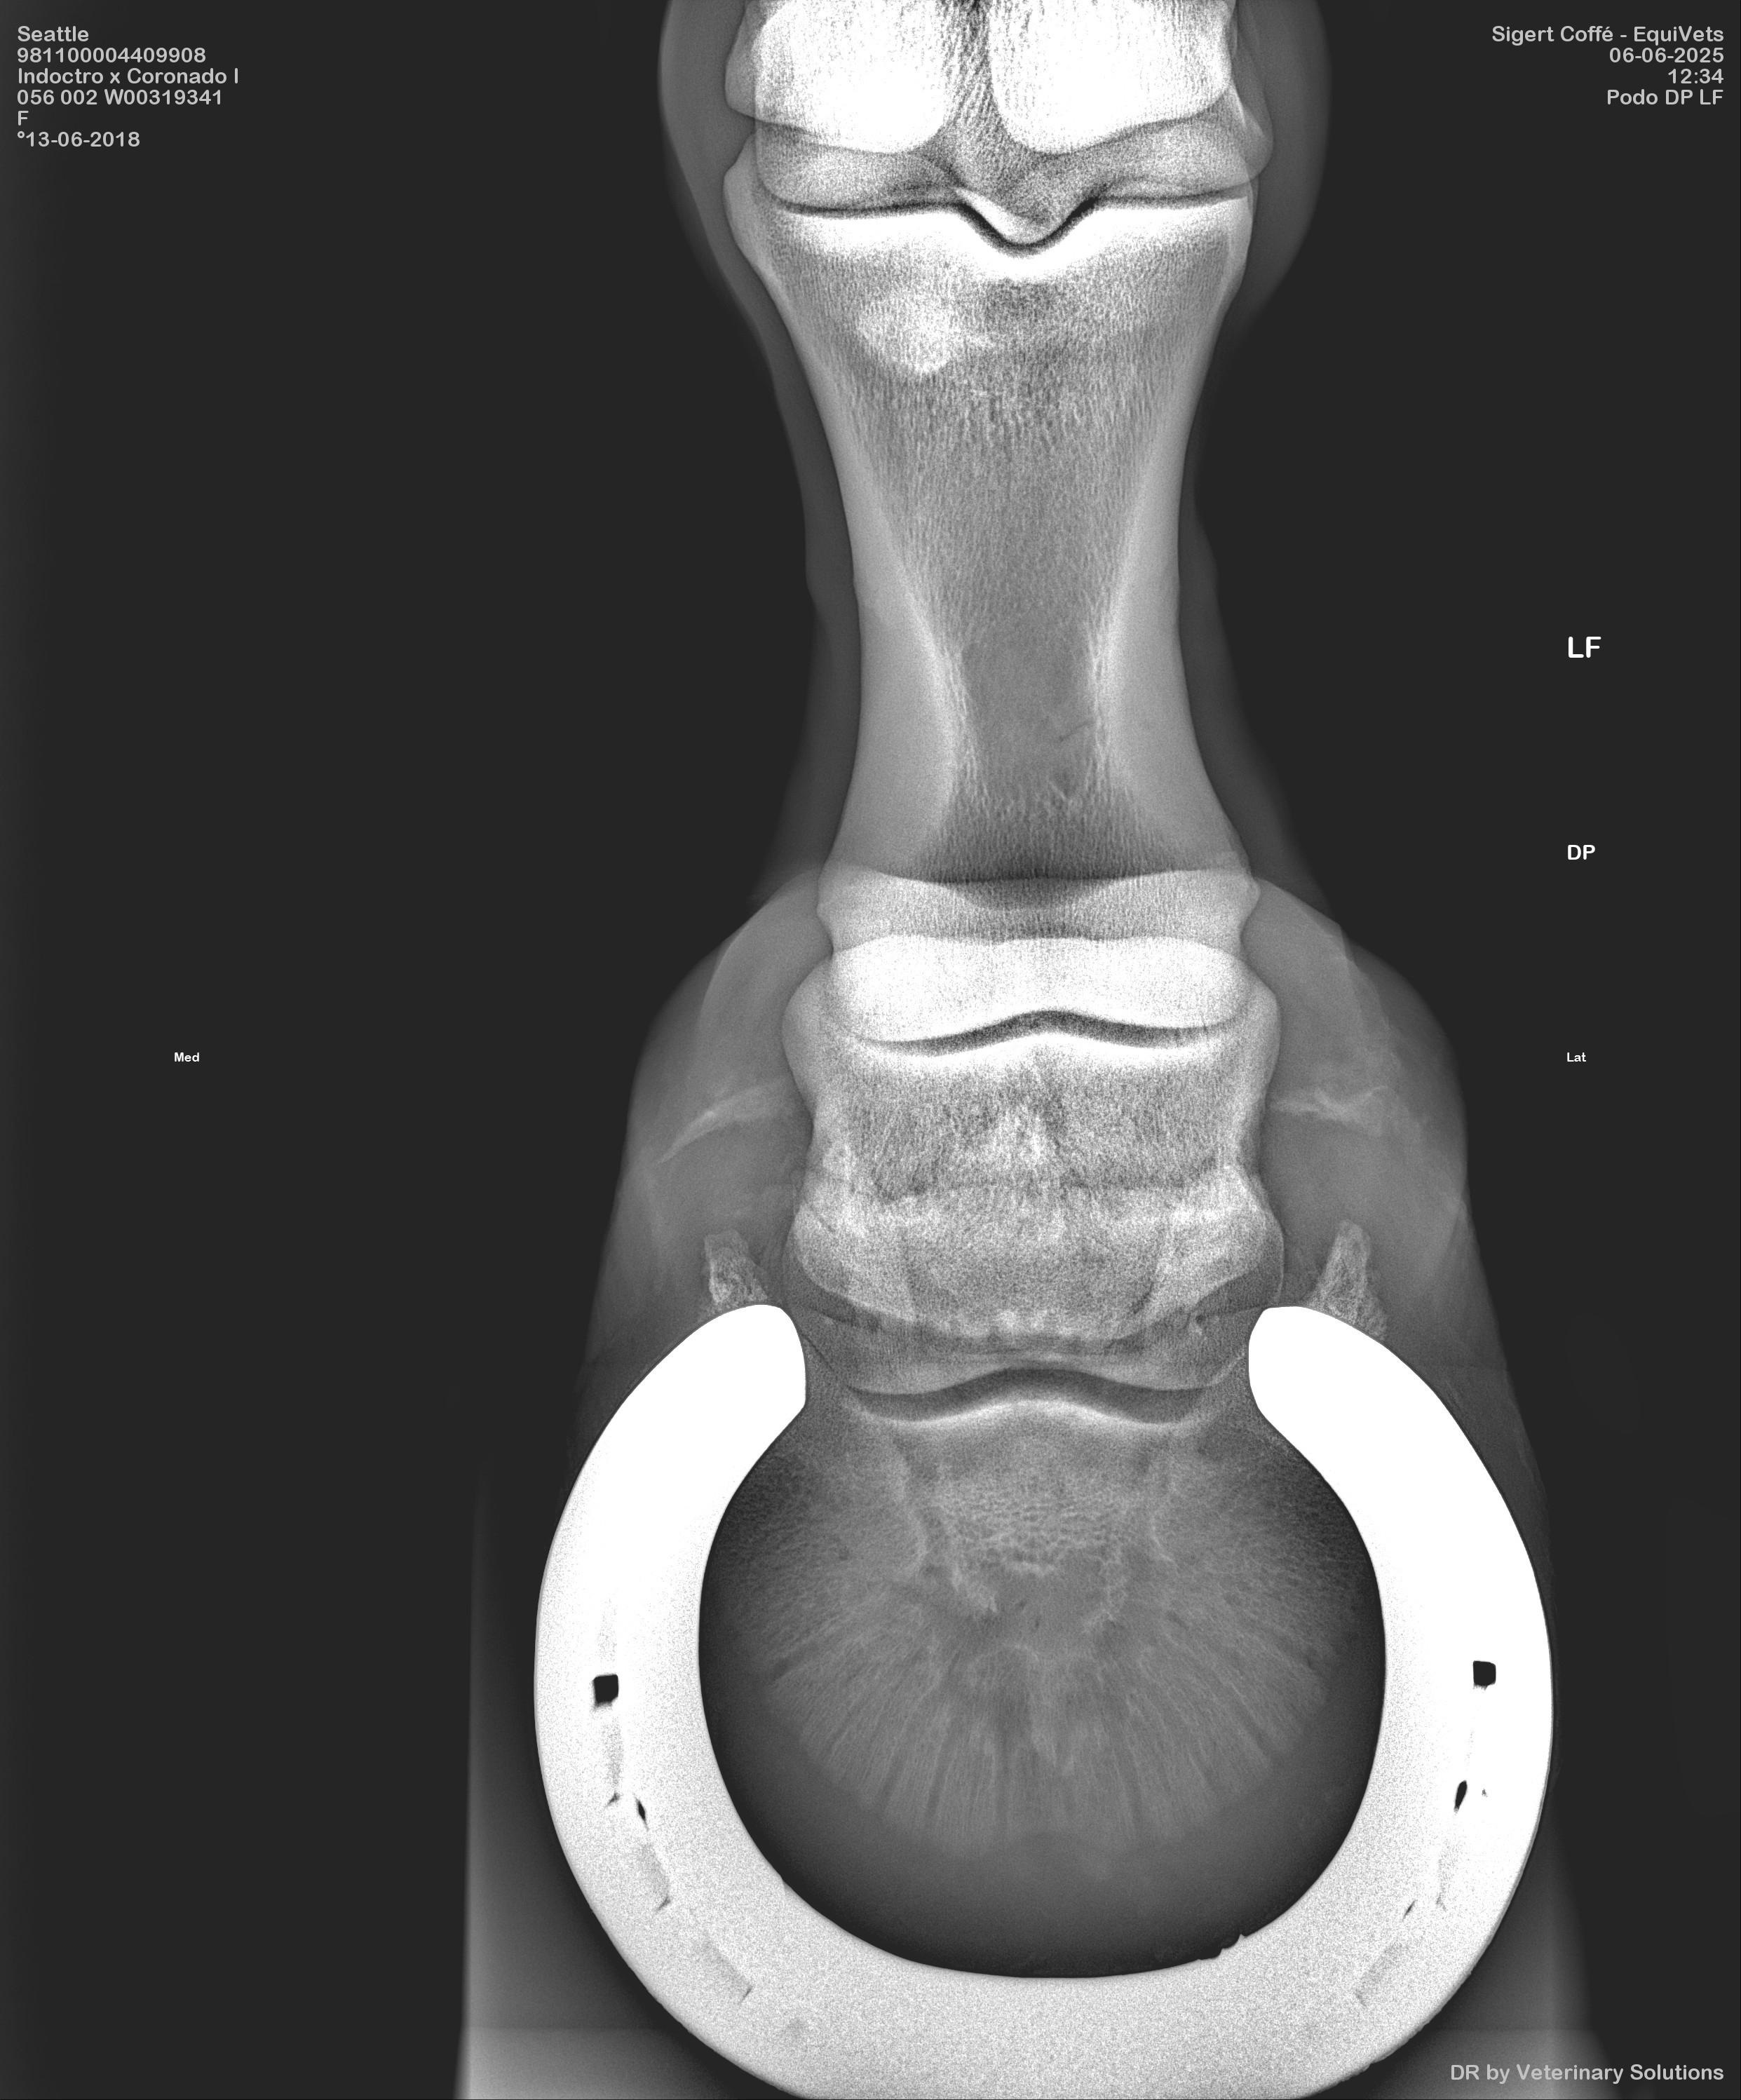

X-rays

Voor röntgenfoto's van een betere kwaliteit (niet in Jpeg), kunt u altijd contact met ons opnemen Neem contact met ons op

x ray 1 rest see link vet check